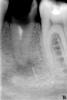

Максич Опубликовано 30 ноября, 2006 Поделиться Опубликовано 30 ноября, 2006 обратился пациент с жалобами на дефект коронки. эндодонтическое лечениепо его словам проводилось 3 года назад. зуб открытый. снимок прилагается. дайте совет. стоит ли пробовать его консервативно лечить?(имеется ввиду эндодонтическое лечение) или проводить резекцию? удалять? Ссылка на комментарий

annda Опубликовано 1 декабря, 2006 Поделиться Опубликовано 1 декабря, 2006 Инструмент доставать,хоть через лунку,хоть через костное окно при резекции... Ссылка на комментарий

Максич Опубликовано 3 декабря, 2006 Автор Поделиться Опубликовано 3 декабря, 2006 [не знаю, насколько правильно я сделал...удалять зуб - жалко, пациенту только 24 года, а уже 5 нет.проконсультировался с хирургом. сказал, что доставать не будет - дескать опасно. я положил в канал турунду, смоченную тубулицидом - на следующий день появились ноющие боли. я еще раз прочистил канал,туда пасту на основе гидрокортизона. назначил найз. прошло только три дня, пока никаких болей. если все будет ОК, то запломбирую, а инструмент - пусть там и будет. не известно, лучше ли будет, если его доставать Ссылка на комментарий